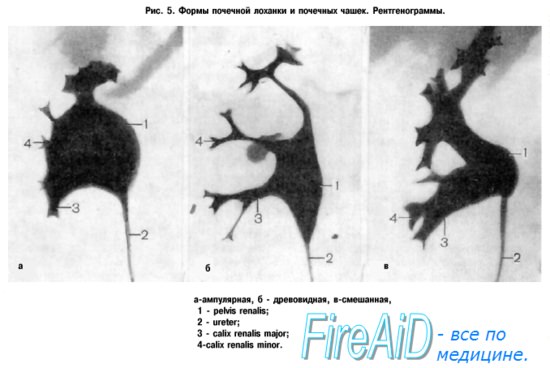

Интраренальная лоханка: рентгеновские снимки и примеры

Раздел: Фотоэссе